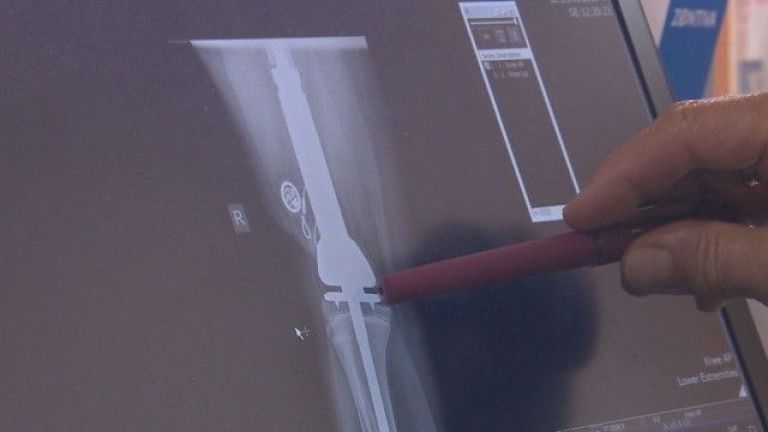

Детето постъпва в лечебното заведение с тежката диагноза Сарком на Юинг, обхващащ цялото ляво бедро. След извършена химиотерапия лекарите пристъпват към унищожаване на тумора - с цялата бедрена кост и заместването ѝ с мегапротеза.

" Тази протеза е такава, че в случай че оперираният крак изостане в растежа си, в съпоставяне със здравия крайник, след привършване на костния напредък на пациентката, ние имаме опция в избран стадий да уеднаквим крайниците, като подменим някой от модулите, които се разполагат в самия имплант ", изясни доктор Кирчо Патриков, гл. помощник в болничното заведение по ортопедия.

Операцията продължава над 4 ч. и е първата такава, осъществена от напълно български екип. Две седмици по-късно 13-годишното дете към този момент прави първите си стъпки.

Протезата от 37 хиляди лева е особено направена в Германия и е платена от Здравната каса.